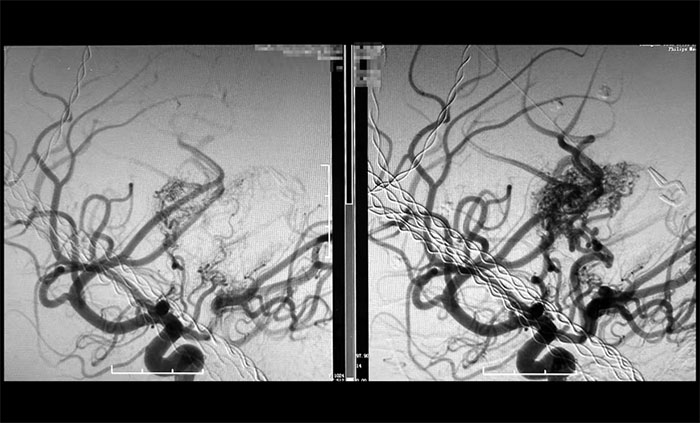

經(jīng)過數(shù)小時的精雕細琢,手術(shù)團隊成功栓塞預期目標責任血管。術(shù)后造影顯示,假性動脈瘤已完全消失,畸形血管團達到預期栓塞效果,所有正常血管血流保持通暢(mTICI 3級)。

巨大腦動靜脈畸形(右),被順利栓塞(左)